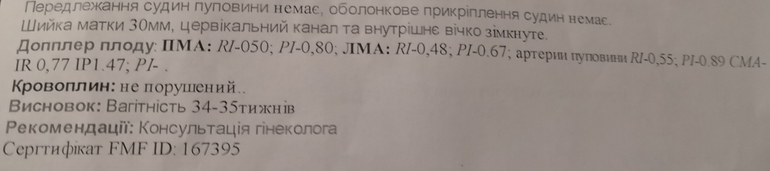

И на платном узи врачу не понравился кровоток в пуповине на шее, тоже поставили однократное обвитие. И в сердце что то смотрела. Сказала похоже на тахикардию, малышка била по датчику сильно и крутилась во все стороны. ЧСС 140 ударов. Врач насторожилась, начала мерять все сосуды заново, смотреть подробнее и ребеночек успокоился как то, она перемеряла кровоток и все было уже хорошо.

Почему такие резкие перемены? Все графики сначала были дикие какие то, то вверх, то вниз, не симметричные, а потом ровные и симметричные... Она мне отдала фото с хорошими ритмами. Я переживаю теперь, накручиваю себя, а вдруг, а вдруг что-то...